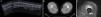

Miositis osificanteSe trata de una formación anormal de hueso laminar maduro dentro de los tejidos blandos esqueléticos donde habitualmente no existe hueso (Figura 9). Su incidencia oscila del 9 al 20% y su patogenia es desconocida, aunque habitualmente se produce de forma secundaria a un traumatismo muscular inicial generalmente en la cara lateral del muslo (músculos vasto lateral y vasto intermedio).

Figura 9. Imagen ecográfica longitudinal panorámica de hematoma intramuscular en glúteo mayor en fase de coagulación.

La clave del diagnóstico se encuentra en objetivar osificación periférica en las pruebas de imagen31. Esta osificación periférica es característica de la miositis osificante y la diferencia del osteosarcoma (Figura 10).

Figura 10. Imágenes de miositis osificante. a) Ecografía panorámica en eje largo de vasto intermedio donde se objetiva osificación completa tras una lesión por contusión. b) Corte axial TC que muestra masa osificada en el vasto interno. c) RM axial T2 STIR. Osificación con médula y cortical óseas maduras.